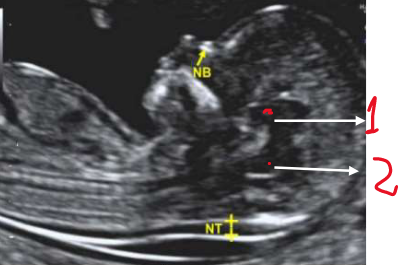

Em relação ao exame obstétrico do primeiro trimestre, podemos afirmar:

I - A mensuração da transluscência nucal é realizada em corte transversal, com o feto em posição neutra.

II - A medida do CCN (comprimento cabeça-nádegas) deve estar entre 45-90 mm para

realização da avaliação morfológica do 1º trimestre.

III - As estruturas assinaladas na imagem abaixo, correspondem ao diencéfalo (1) e ao tronco cerebral/ponte e bulbo (2).

IV - A imagem deve estar ampliada de maneira que apenas a cabeça e a parte superior do tórax sejam vistas.